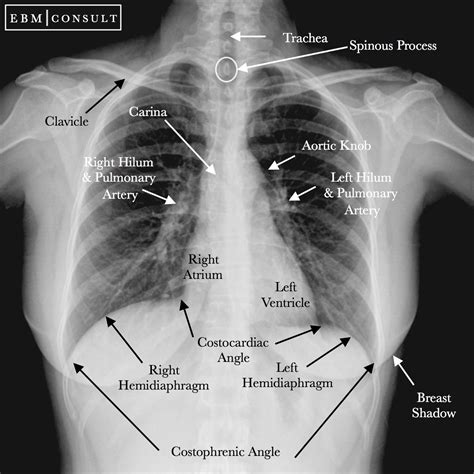

X-rays (Chest Radiographs)

Often one of the first tests performed, a chest X-ray can reveal abnormalities in the lungs, pleura, or chest wall. While not definitive for mesothelioma, it can show fluid buildup (pleural effusion) or thickening of the pleura, which may prompt further investigation. It's a quick, non-invasive starting point.